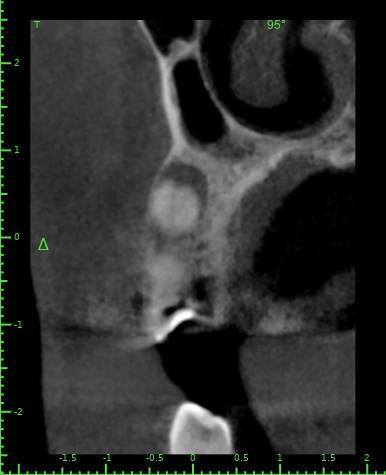

Здравствуйте, появился полгода назад свищ на десне, заполняется и лопается, затягивается и снова появляется, спустя пару месяцев обратился в стоматологию, на снимке ничего критичного не увидели, отправили домой наблюдать тип, еще прошло 3 месяца, так и не проходит и хуже не стало, болей нет никаких, только небольшая если трогать в районе свища, пойдя в другую стоматологию, сделали снимок и так же непонятно что и почему, пошел на КТ, и обратно в стоматологию, есть какая то полость, можно попробовать но нет гарантии, что пройдет, прикрепляю снимок К

ТРезультаты и плюс программа для открытия